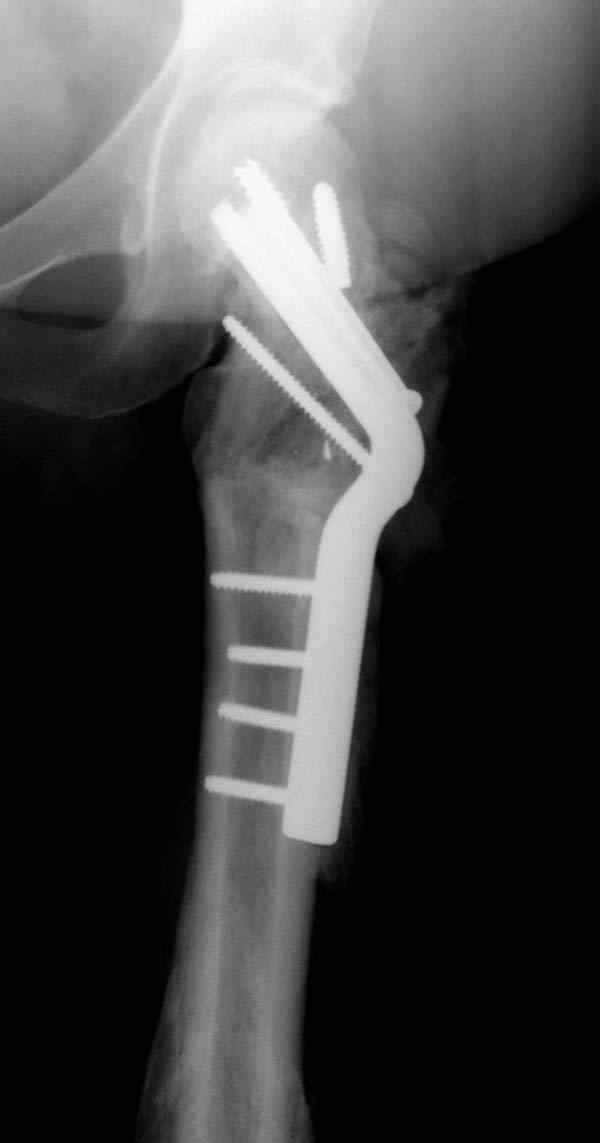

Наверно, вариант с вальгизирующей остеотомией с фиксацией blade plate или DHS более щадящий. А диафиз можно рефиксировать ретроградно. Или про эндопротезирование с очень длинной ножкой подумать.

Несмотря на пессимистические прогнозы, у молодых

коррегирующая вальгусная остеотомия является более

приемлемым.

Представленные случаи доказательства тому, что еще

имеется резервы на восстановление даже у 5-6 месячных ложных суставов шейки.